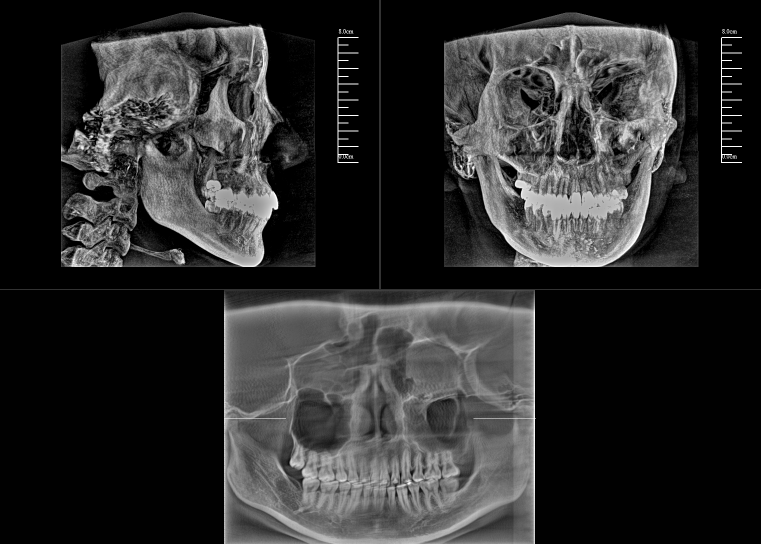

CBCT,全稱“錐束計(jì)算機(jī)斷層掃描(Cone-Beam Computed Tomography,CBCT)”,由球管和平板探測器組成。與全科CT的閉環(huán)圓孔設(shè)計(jì)不同,數(shù)字化口腔CBCT采用開放式結(jié)構(gòu)以保持其靈活性。

對于口腔內(nèi)科疾病,牙片和全景片已具有較高診斷效果;但對于牙體牙髓病,2D成像較容易發(fā)生影像重疊的情況,無法進(jìn)一步明確根管和其他周圍組織的三維信息,容易出現(xiàn)漏診或誤診根裂的情況。這就需要三維斷層成像,即數(shù)字化口腔CBCT。

數(shù)字化口腔CBCT是從三維的角度,即矢狀位、冠狀位和橫斷位來顯示病變組織和正常組織結(jié)構(gòu),有效的避免了2D圖像固有的缺陷,如正常組織器官的影像重疊,投射角度變化所致的影像扭曲、變形等,大大提高了診斷能力。

數(shù)字化口腔CBCT能在十幾秒時間內(nèi)完成患者口腔掃描,進(jìn)而生成高精度的三維影像,徹底解決了牙片機(jī)、全景機(jī)等傳統(tǒng)口腔X射線設(shè)備影像重疊、畸變的問題。可以360°全方位立體觀測牙床的骨質(zhì)密度、牙槽骨本身的高度、寬度等數(shù)據(jù),不僅能重建整個顱面區(qū)的結(jié)構(gòu),對頜面骨質(zhì)結(jié)構(gòu)進(jìn)行測量,而且還能重建精細(xì)的解剖細(xì)節(jié)。